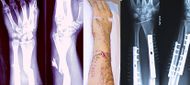

| منظر داخلي وخارجي لذراع به كسر مركب. كلا منهما قبل وبعد الجراحة. | |

- كسر مركب: وفيه تنكسر العظمة ويتمزق الجلد الذي فوقها.

اكتشاف الكسور

العلاج

- - تتوقف العملية الجراحية على نوع الكسر ، امكانيات الجراح العملية ، الامكانيات المتوفرة بحجرة العمليات .

- -العملية قد تكون بسيطة 1-2 براغي ،او DHS ، استبدال مفصل الورك THP .